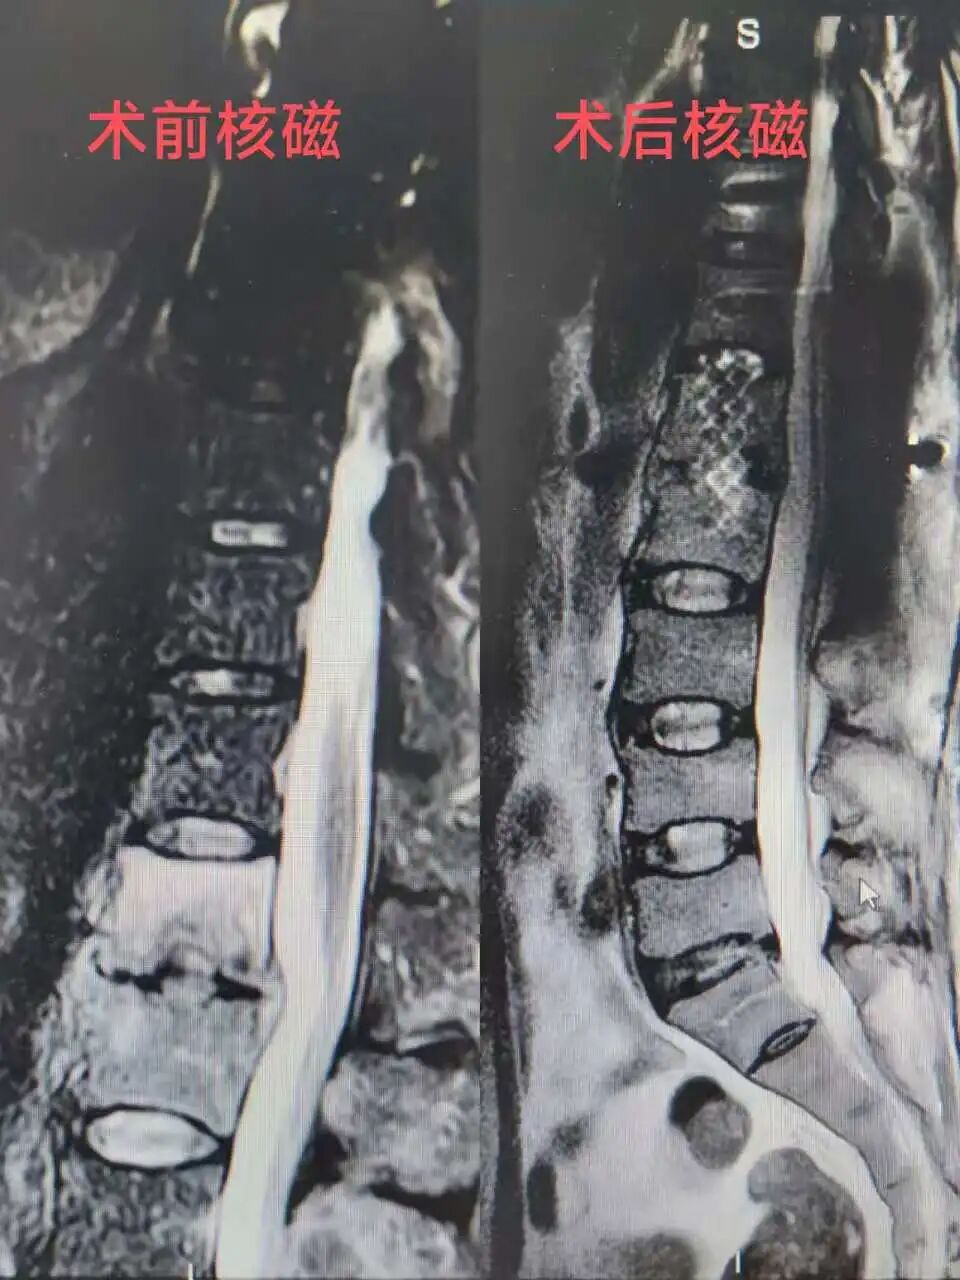

62岁的李先生因颈椎结核入院,病情复杂、治疗周期长,一家人正为后续手术费用发愁。科室第一时间评估并协助申请,基金迅速为其提供2000元专项补助。李先生家人感慨道:“在最难的时候,这笔补助真是及时雨,让我们能安心治病,也看到了希望。”